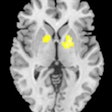

MRI shows that diabetes leads to loss of brain volume